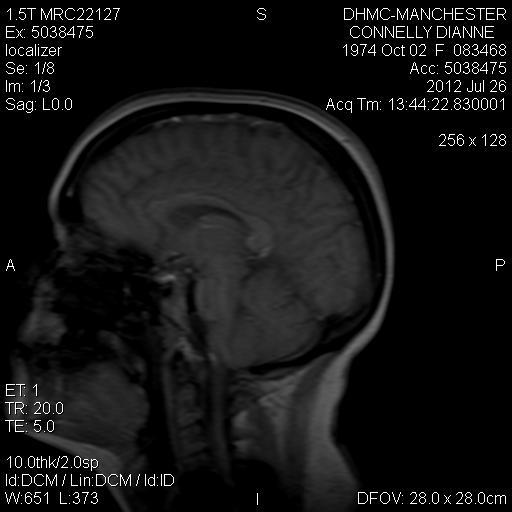

Yeah, I actually sent them directly to you when we were talking about it before. There's the issue with the retroflexed odontoid and then the brain MRI shows a lot of crowding and no space between the cerebellum and brainstem....if you don't have still I'll try to find and repost.